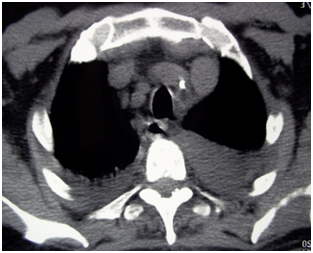

A 59-year-old Tunisian patient, with no notable pathological history, was hospitalized in our department for the management of acute febrile dyspnea with a low-grade bilateral pleural effusion and a bilateral bronchial syndrome on the chest x-ray. The examination noted a fever at 40°C and snoring rales at both lung fields with no other abnormalities. Biology showed a marked inflammatory syndrome with a C–reactive protein level of 93.4mg/l and an erythrocyte sedimentation rate at 90mmH1. The blood count showed leukocytosis at 12500/mm3 with a predominance of neutrophils (75%). Intravenous antibiotic therapy with Cefotaxime 3g/day was prescribed but without any improvement. Explorations for active tuberculosis were negative (tuberculin intradermal reaction, search for Koch bacillus in sputum, gastric fluid and urine, and Quantiferon test). Thoracic CT confirmed a bilateral pleural effusion of low-to moderate abundance with no parenchymal lung lesions or associated mediastinal lymphadenopathy (Figure 1).

Figure 1 Axial CT-scan of the thorax: bilatreal pleural effusion.